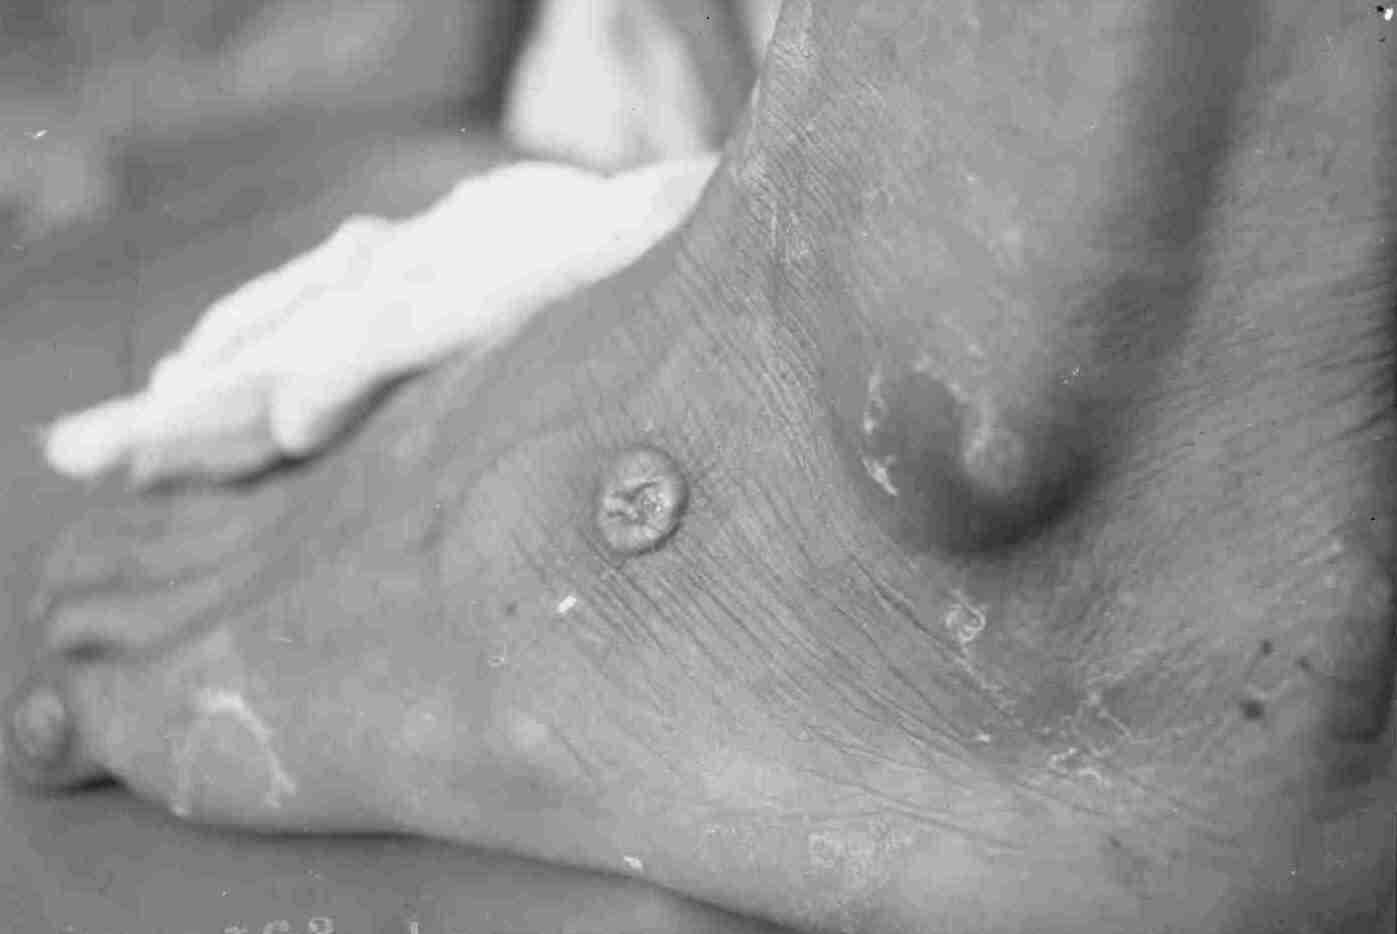

감염 후 약 1년이 지나면, 암컷 벌레는 피부 표면 가까이로 이동하여 물집을 형성한다.[2] 이 물집은 터지면서 궤양을 형성하고, 감염된 사람이 상처 부위를 물에 담그면 암컷 벌레는 수십만 마리의 유충을 물속으로 방출한다. 이 유충은 물속에서 최대 3주까지 생존할 수 있다.[22] 유충은 물벼룩에게 섭취되어야 생존 및 발달할 수 있으며,[20] 물벼룩 체내에서 최대 4개월까지 생존하며[22] 발달하여 다시 사람을 감염시킬 수 있는 상태가 된다. 따라서 이 질병이 계속 유행하기 위해서는 매년 사람에게 감염이 일어나야 한다.[23]

메디나충증의 첫 번째 징후는 감염 후 약 1년이 지나 성체 암컷 벌레가 몸 밖으로 나올 준비를 할 때 나타난다.[2] 벌레가 몸 밖으로 나올 부위, 주로 다리나 발로 이동하면서 일부 감염자는 알레르기 반응을 보일 수 있는데, 이는 두드러기, 발열, 현기증, 메스꺼움, 구토, 설사 등의 증상을 포함한다. 벌레가 목적지에 도착하면 피부 아래에 체액으로 가득 찬 물집을 형성한다. 이 물집은 1~3일 동안 점점 커지면서 심한 작열감을 유발하고, 결국 터지면서 작은 개방성 상처(궤양)를 남긴다.[2] 벌레는 이 상처를 통해 몇 주에서 몇 달에 걸쳐 서서히 몸 밖으로 나오며, 이 과정은 극심한 통증을 동반한다.

감염된 사람이 상처를 물에 담그면 벌레는 유충을 물속으로 배출한다. 벌레가 나오면서 생긴 개방성 상처는 종종 세균에 감염되어 발적과 부어오름을 유발하고, 농양을 형성하며, 심한 경우 괴저, 패혈증, 또는 파상풍으로 이어질 수도 있다.[4] 만약 이차 감염이 관절(일반적으로 발목) 근처에서 발생하면, 관절 손상으로 인해 강직증, 관절염 또는 구축(관절 운동 범위 제한)이 발생할 수 있다.

감염된 사람은 보통 한 마리 이상의 벌레를 가지고 있으며, 평균적으로 1인당 1.8마리의 벌레가 나타나고, 많게는 40마리까지 동시에 다른 물집에서 나올 수 있다. 벌레의 약 90%는 다리나 발에서 나오지만, 신체의 다른 부위에서도 나타날 수 있다.